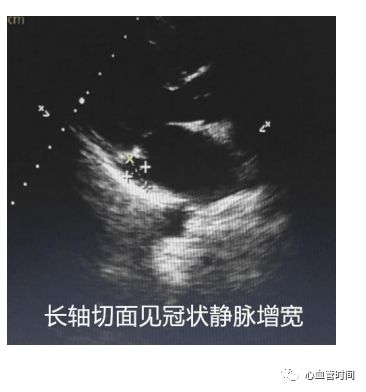

冠状静脉正常冠状静脉在长轴切面上看基本是个

「点」,增宽时要结合其他切面

测量内径大小并分析病因。

冠状静脉正常冠状静脉在长轴切面上看基本是个

「点」,增宽时要结合其他切面

测量内径大小并分析病因。